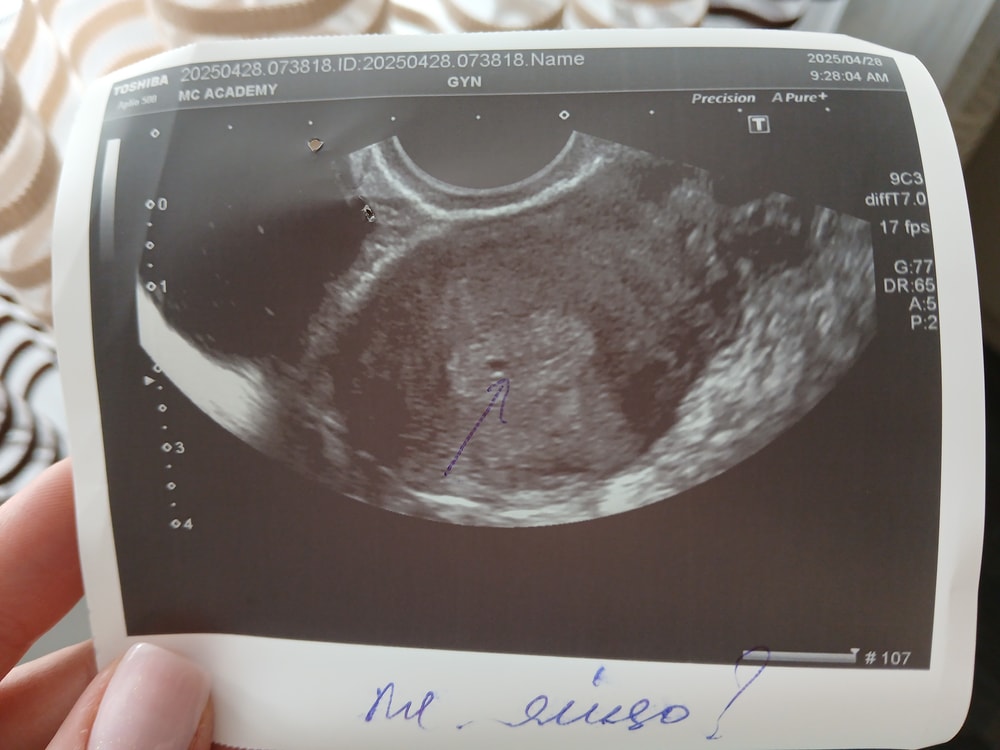

Девочки, здравствуйте. У меня такая ситуация, задержка 15 дней, все тесты отрицательные. Сегодня пошла на узи, оно получилось какое то неоднозначное.. врач конкретно сказать не смогла есть ли беременность, срок уже должен был показать 100% беременность, но при этом следы жидкости присутствуют, возможно месячные пойдут. Врач еще предположила, внематочную.

Кровь на ХГЧ пойду сдавать только завтра. С первым ребёнком при такой задержке уже был виден маленький эмбриончик. Даже не знаю что думать...